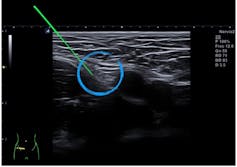

Nuestro estudio consistió en un ensayo clínico donde se evaluaban los efectos de la neuromodulación percutánea. Esta técnica consiste en introducir una aguja de acupuntura o punción seca guiada ecográficamente hasta poner la punta en contacto con un nervio para que, a través de impulsos eléctricos, la estimulación del nervio produzca diversos efectos en función del tipo de corriente (analgesia, disminución o aumento del tono muscular…).